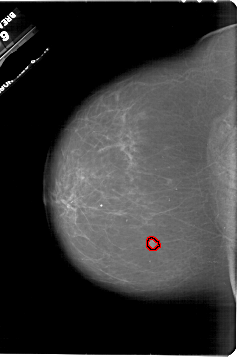

A_1848_1.RIGHT_MLO

RIGHT_MLO LINES 5956 PIXELS_PER_LINE 4336 BITS_PER_PIXEL 12 RESOLUTION 43.5 OVERLAY

FILE: A_1848_1.RIGHT_MLO.OVERLAY

TOTAL_ABNORMALITIES 1

ABNORMALITY 1

LESION_TYPE MASS SHAPE IRREGULAR MARGINS ILL_DEFINED

ASSESSMENT 4

SUBTLETY 2

PATHOLOGY MALIGNANT

TOTAL_OUTLINES 1

BOUNDARY